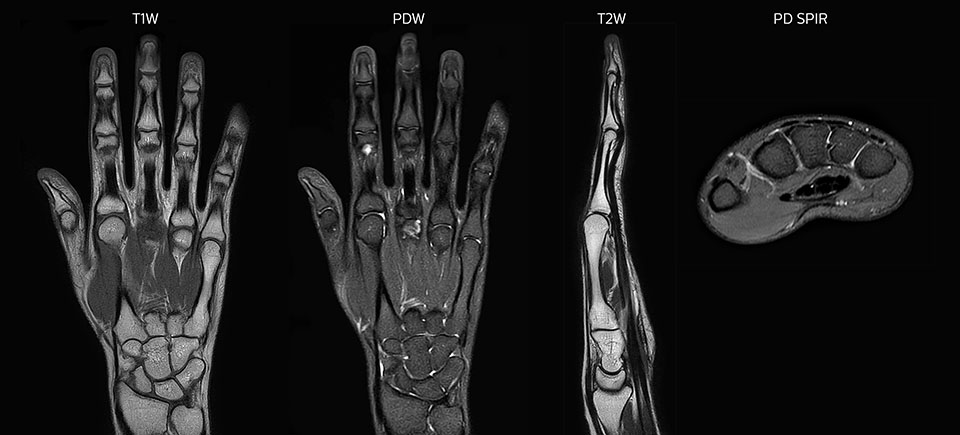

Bildgebung der Hand mit Prodiva deckt die Fingerspitzen und das gesamte Handgelenk ab. Die dS MSK M Spule ist anwenderfreundlich.

Scandauer: 2:55 Minuten, FOV: 160 mm, erfasste Voxel: 0,55 x 0,83 x 3,0 mm.

Scandauer: 04:19 Minuten, FOV: 160 mm, erfasste Voxel: 0,55 x 0,80 x 3,0 mm.

Scandauer: 02:50 Minuten, FOV: 160 mm, erfasste Voxel: 0,70 x 0,99 x 3,0 mm.